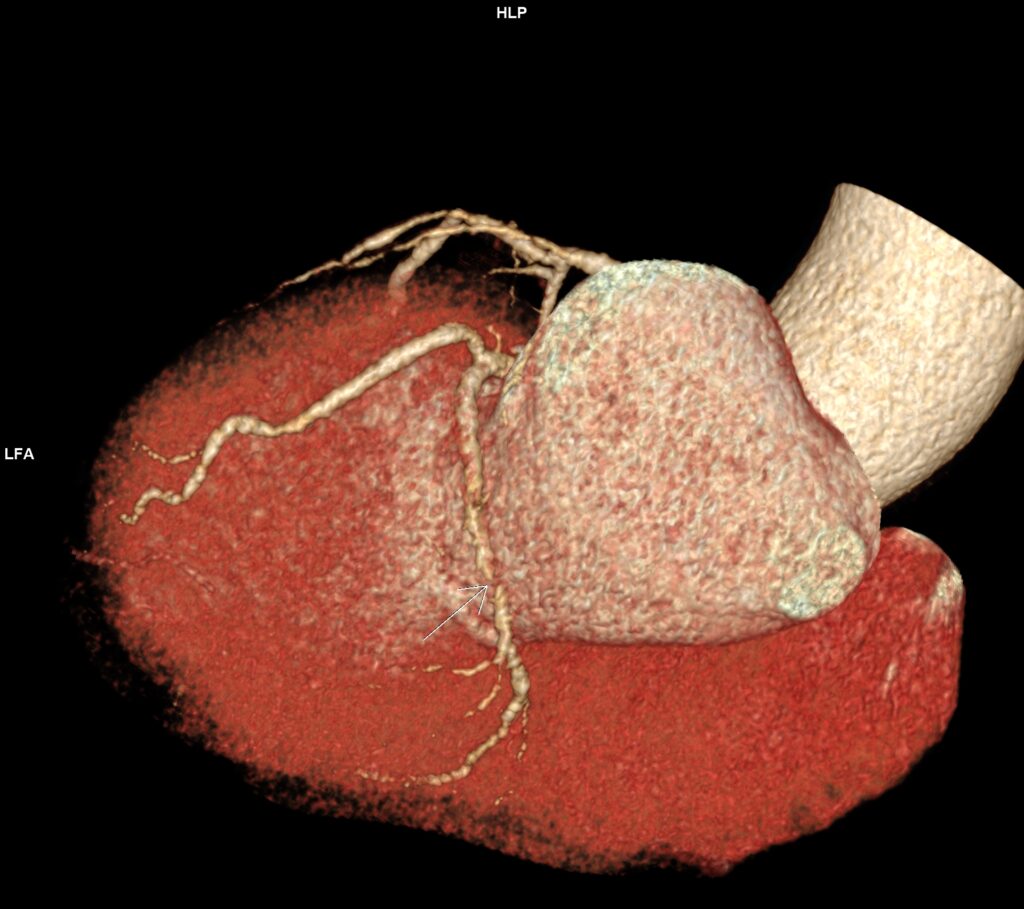

Figura 8: reconstrucție volumică (VRT) din examinarea inițială cu evidențierea stenozei severe de la nivelul arterei circumflexe

Figurile 9 si 10: reconstrucție multiplanară din examinarea recentă cu evidențierea stentului permeabil de la nivelul arterei circumflexe

Discuţie caz nr 114: Examinarea cardioCT are indicație de clasa 1 la pacienții cu sindroame coronariene cronice; la acest pacient se poate observă evoluția în dinamică a unor plăci de la nivelul arterei descendente anterioare – indicația de repetare a investigației s-a datorat faptului că pacientul acuză dureri de tip anginos nou apărute la 5 luni după coronarografia cu implantare de stent pe arteră circumflexă.

DE LUAT ACASĂ!!! Examinarea cardioCT este indicată la pacienții cu sindroame coronariene cronice datorită valorii predictive negative mari, are tendința de a supraestima gradul de stenoză mai ales când este și calciu în placă și este urmată de coronarografia invazivă pentru diagnostic și, eventual, tratament în cazul în care se decelează stenoze severe (reducere de lumen mai mare de 70%).